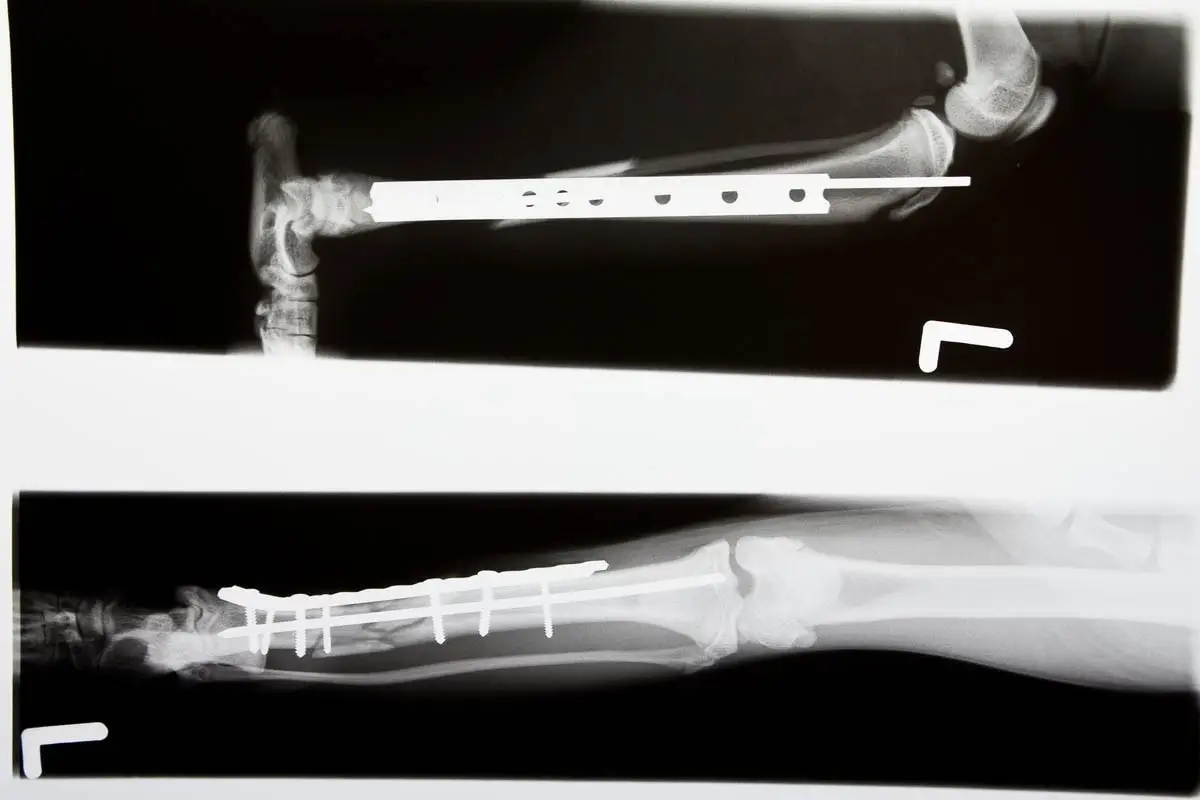

Fijación interna:

Imagem R. Fassbind, Shutterstock

- Cirugía para realizar huesos y colocar tornillos, alfileres y varillas de hueso para mantener las piezas juntas mientras se cura.